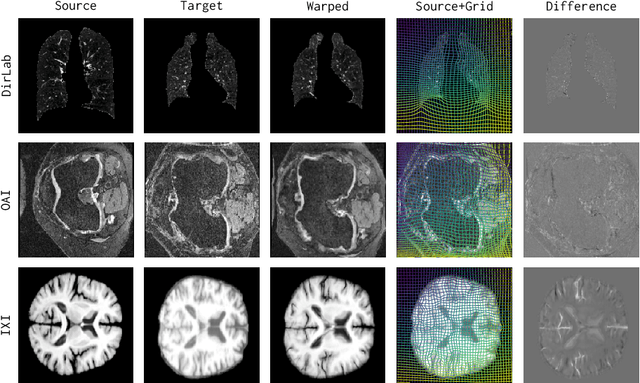

Abstract:Conventional medical image registration approaches directly optimize over the parameters of a transformation model. These approaches have been highly successful and are used generically for registrations of different anatomical regions. Recent deep registration networks are incredibly fast and accurate but are only trained for specific tasks. Hence, they are no longer generic registration approaches. We therefore propose uniGradICON, a first step toward a foundation model for registration providing 1) great performance \emph{across} multiple datasets which is not feasible for current learning-based registration methods, 2) zero-shot capabilities for new registration tasks suitable for different acquisitions, anatomical regions, and modalities compared to the training dataset, and 3) a strong initialization for finetuning on out-of-distribution registration tasks. UniGradICON unifies the speed and accuracy benefits of learning-based registration algorithms with the generic applicability of conventional non-deep-learning approaches. We extensively trained and evaluated uniGradICON on twelve different public datasets. Our code and the uniGradICON model are available at https://github.com/uncbiag/uniGradICON.